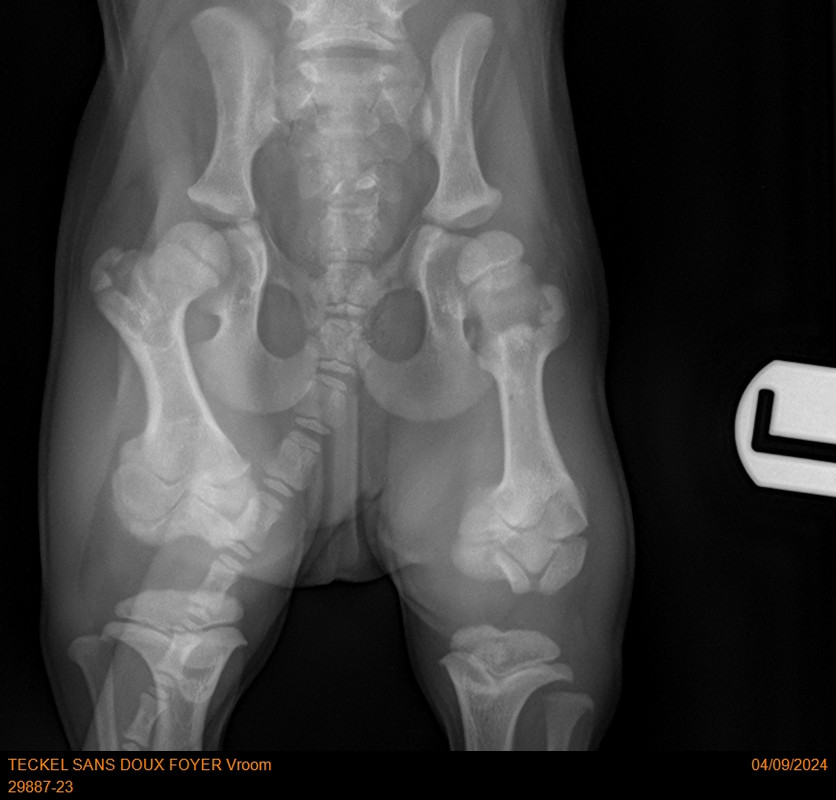

[Image: 29887-23-TECKEL-SANS-DOUX-FOYER-Vroom-20788.jpg]

[Image: 29887-23-TECKEL-SANS-DOUX-FOYER-Vroom-20789.jpg]

[Image: 29887-23-TECKEL-SANS-DOUX-FOYER-Vroom-20790.jpg]

Sur la deuxième radios les 2 cotés ne sont pas identiques. C’est là le problème ?

Oui, son problème de rotule au genou se répercute sur la hanche, d’où la nécessité de l'opérer de toute urgence sinon il risque une dysplasie de la hanche. Et aussi ne pas grandir normalement !